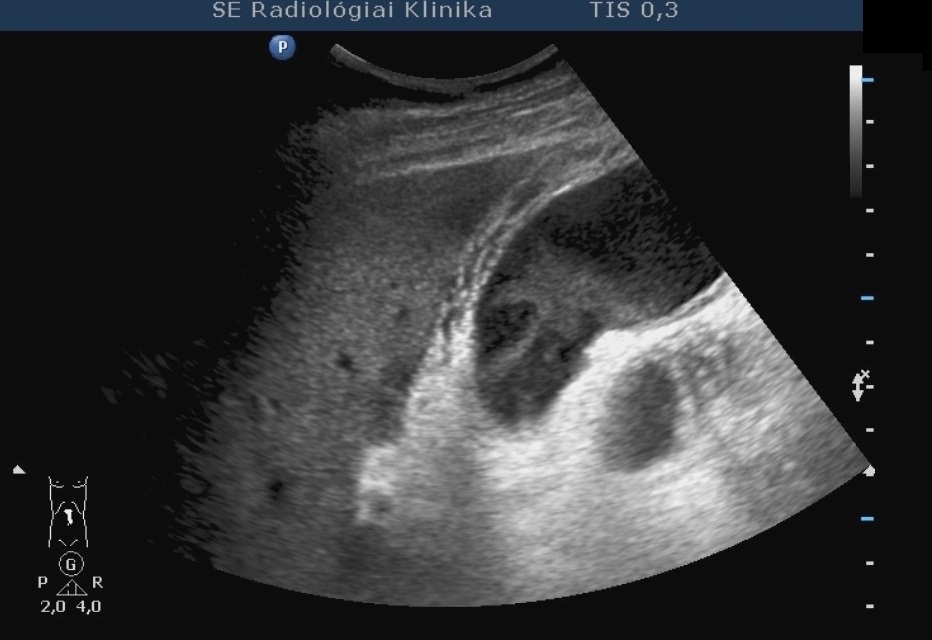

14.5.5. Cysts

The spleen cysts occur less frequently then the liver cysts, their morphological appearence is similar to that of the liver cysts (homogeneous, cystic content, sharp contour, thin wall, sometimes some thin septa). Most of them is detected only accidentally. It has a therapeutic consequence if its size increases resulting symptoms for the patient by the compression of the sorrounding tissues (Figure 47, 48).

Figure 48: Spleen cyst, contrast enhanced CT

A májcysták alkoholos sclerotisatiojához hasonlóan ezek a panaszt okozó lépcysták is kezelhetők (49. ábra), de nagyobb körültekintést igényelnek, mert a jelentősen vascularisaltabb lépparenchyma miatt a bevérzés esélye jóval nagyobb.

49. ábra Lépcysta rtg. felvétel, alkoholos sclerotisatio előtti kontrasztfeltöltés

Similarly to the alcoholic sclerotisation of the liver cysts, these symptomatic splenic cysts can be also treated (Figure 49), but more circumspection is needed, since the chance of hemorrhage is higher because of the notably vascularisated splenic parenchyma.